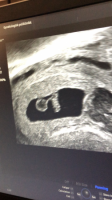

han tok nok flere målinger som i gjennomsnitt gav 6+3, mens denne ene målingen kanskje viste tilsvarende 6+6. I de fleste tilfeller er det uansett menstermin som "teller" frem til ordinær UL

Fikk høre hjertet også- veldig deilig!